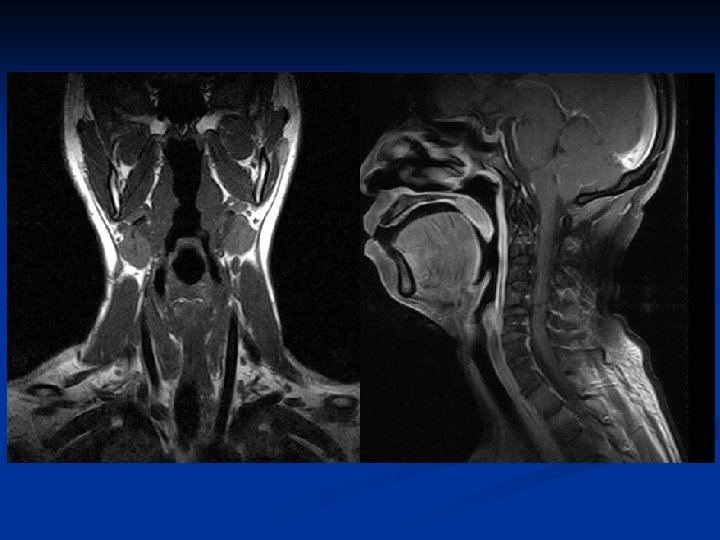

Neck space & vessels

Carotid spaces n Contents: Internal carotid artery Internal jugular vein CN IX, X, XII: nasopharyngeal CS CN X only: oropharyngeal & hypopharyngeal CS Sympathetic plexus Lymph nodes